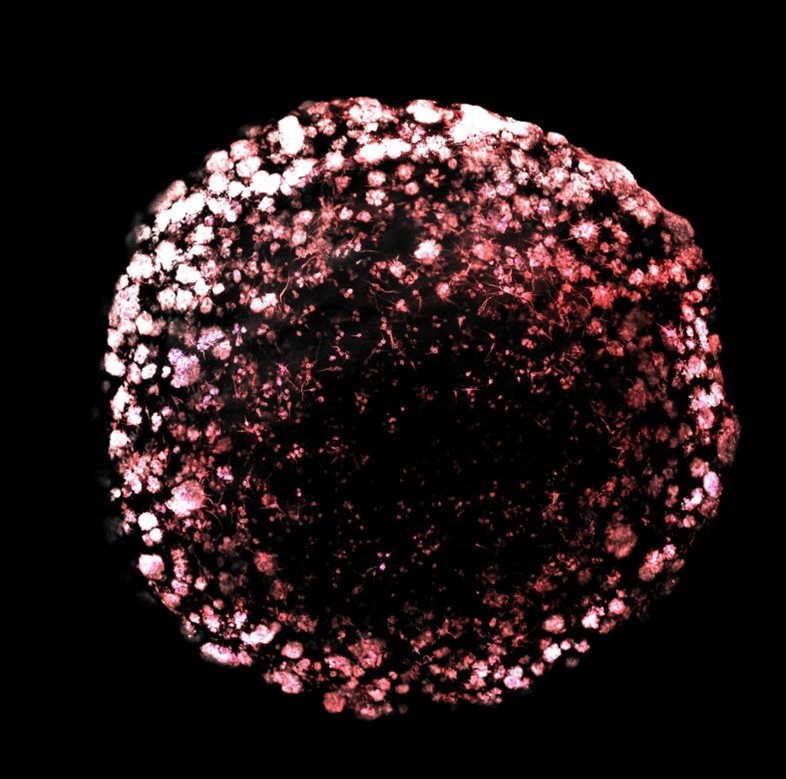

Structures de type TNT et extensions de type TM dans un organoïde tumoral de CSG

Les organoïdes tumoraux constituent une méthode de culture tridimensionnelle ad hoc, qui permet une croissance cellulaire à long terme tout en préservant l’identité des cellules souches et en reconstituant, dans une certaine mesure, l’hétérogénéité morphologique et phénotypique de la tumeur d’origine. Image à fluorescence représentative d’un organoïde tumoral de CSG après 23 jours de culture, coloré pour l’anti-tubuline alpha (microtubules, blanc) et la phalloïdine (actine, rouge). Différents types de connexions sont présents et coexistent à l’intérieur de l’organoïde. Copyright : Institut Pasteur/Chiara Zurzolo